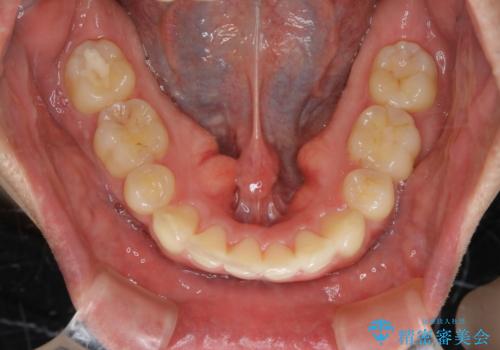

がたつき、口ゴボ(出っ歯)、真ん中のずれを抜歯矯正治療で治す。ワイヤー矯正治療

- 口元の突出感とがたつきを気にして来院されました。

突出感とがたつきの改善を行うために大きなスペースが必要であったため、親知らず以外の歯を4本歯を抜歯する計画を立てました。